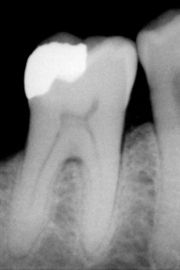

Röntgenaufnahme eines Zahnes mit Amalgamfüllung.